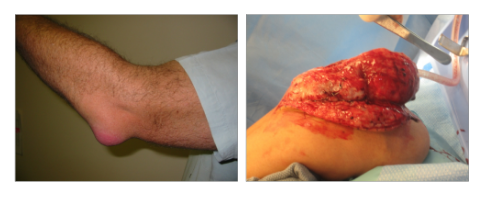

What is this?

AKA?

- Radial/Ulnar Nerve palsies

- saturday night palsies- pass out on their arm